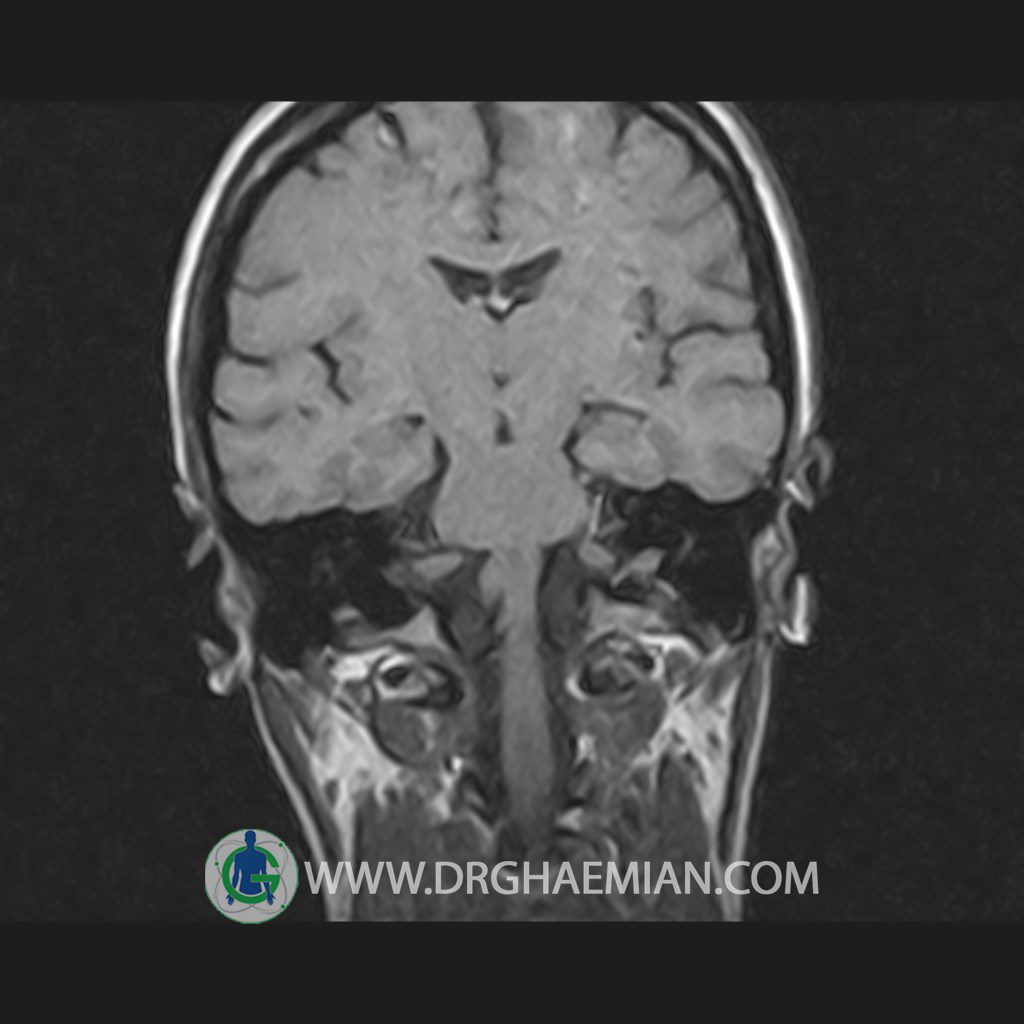

پزشکان اغلب از تصویربرداری ام آر آی برای تشخیص و درمان عارضه های پزشکی که فقط با استفاده از اشعه ایکس یا میدان مغناطیسی و امواج رادیویی قابل مشاهده است، استفاده می کنند. دستگاه ام آر آی تصاویر دقیق از ساختار های داخلی بدن ایجاد می کند. در این کیس هیپرپلازی هیپوفیز و آدنوم مشاهده می شود.

HYPOPHYSIS MRI

(with and without contrast)

Technique: Axial , coronal T1 , Axial , coronal , sagittal T2 , Axial, coronal T1 post Gd & 64 dynamic thin coronal slices.

The sella shows normal size , position and configuration .

The borders of its floor and walls are smooth and sharply defined .

The infundibulum is centered and of normal size .

The optic chiasm and suprasellar spaces appear normal .

The cavernous sinus and imaged portions of the internal carotid artery and carotid siphon are unremarkable .

Evaluable portions of the neurocranium show no abnormalities .

The sphenoid sinus is clear and pneumatized .

– Mild convexity at superior border of pituitary gland with post contrast homogeneous enhancement suggestive for pituitary hyperplasia & iso signal adenoma

is seen